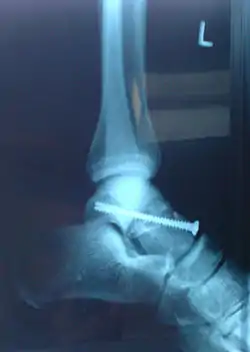

Imagerie d'une fracture de l'astragale, évènement-clé du roman. | ||||||||

En sautant d'un mur pour s'échapper de prison, Anne se brise l'astragale, un petit os du tarse. Elle se traîne sur le bord de la route nationale, hèle un poids lourd. L'homme, qui a peur des responsabilités, ne prend pas en charge Anne mais stoppe pour elle une voiture. Son conducteur, Julien, est lui aussi un repris de justice.